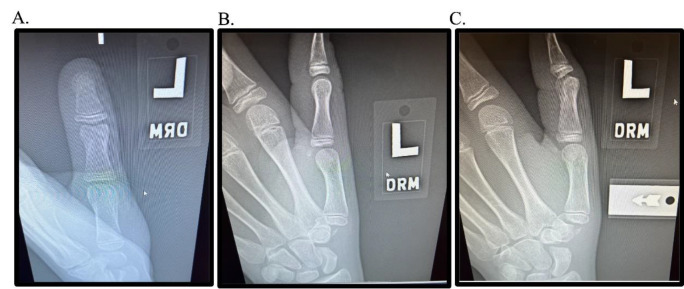

小儿班尼特等效型骨折是一种罕见但又重要的发病率和诊断复杂性的来源。尽管儿科患者具有显著的重塑潜力和弹性,但如果处理不当,这些损伤会带来多种后遗症,如残余畸形、疼痛、功能限制和前瞻性加速关节病。鉴于文献的缺乏和前瞻性、严格的试验的缺乏,这些损伤的最佳管理仍然存在争议。本研究展示了作者对两例儿童班尼特等效骨折的经验,一例保守治疗,一例手术治疗,强调了提供者在识别和治疗这些损伤时保持警惕和注意力的必要性。

Pediatric Bennett-equivalent type fractures represent an uncommon yet consequential source of morbidity and diagnostic complexity. Despite the remarkable remodeling potential and resiliency of the pediatric patient population, if managed inappropriately, these injuries are associated with multiple sequelae such as residual deformity, pain, functional limitations, and prospective accelerated arthrosis. Given the paucity of literature and absence of prospective, rigorous trials, the optimal management of these injuries remains contentious. The present study exhibits the authors' experience with two pediatric Bennett-equivalent fractures, one managed conservatively and one operatively, highlighting the necessity for provider vigilance and attentiveness in recognizing and treating these injuries.